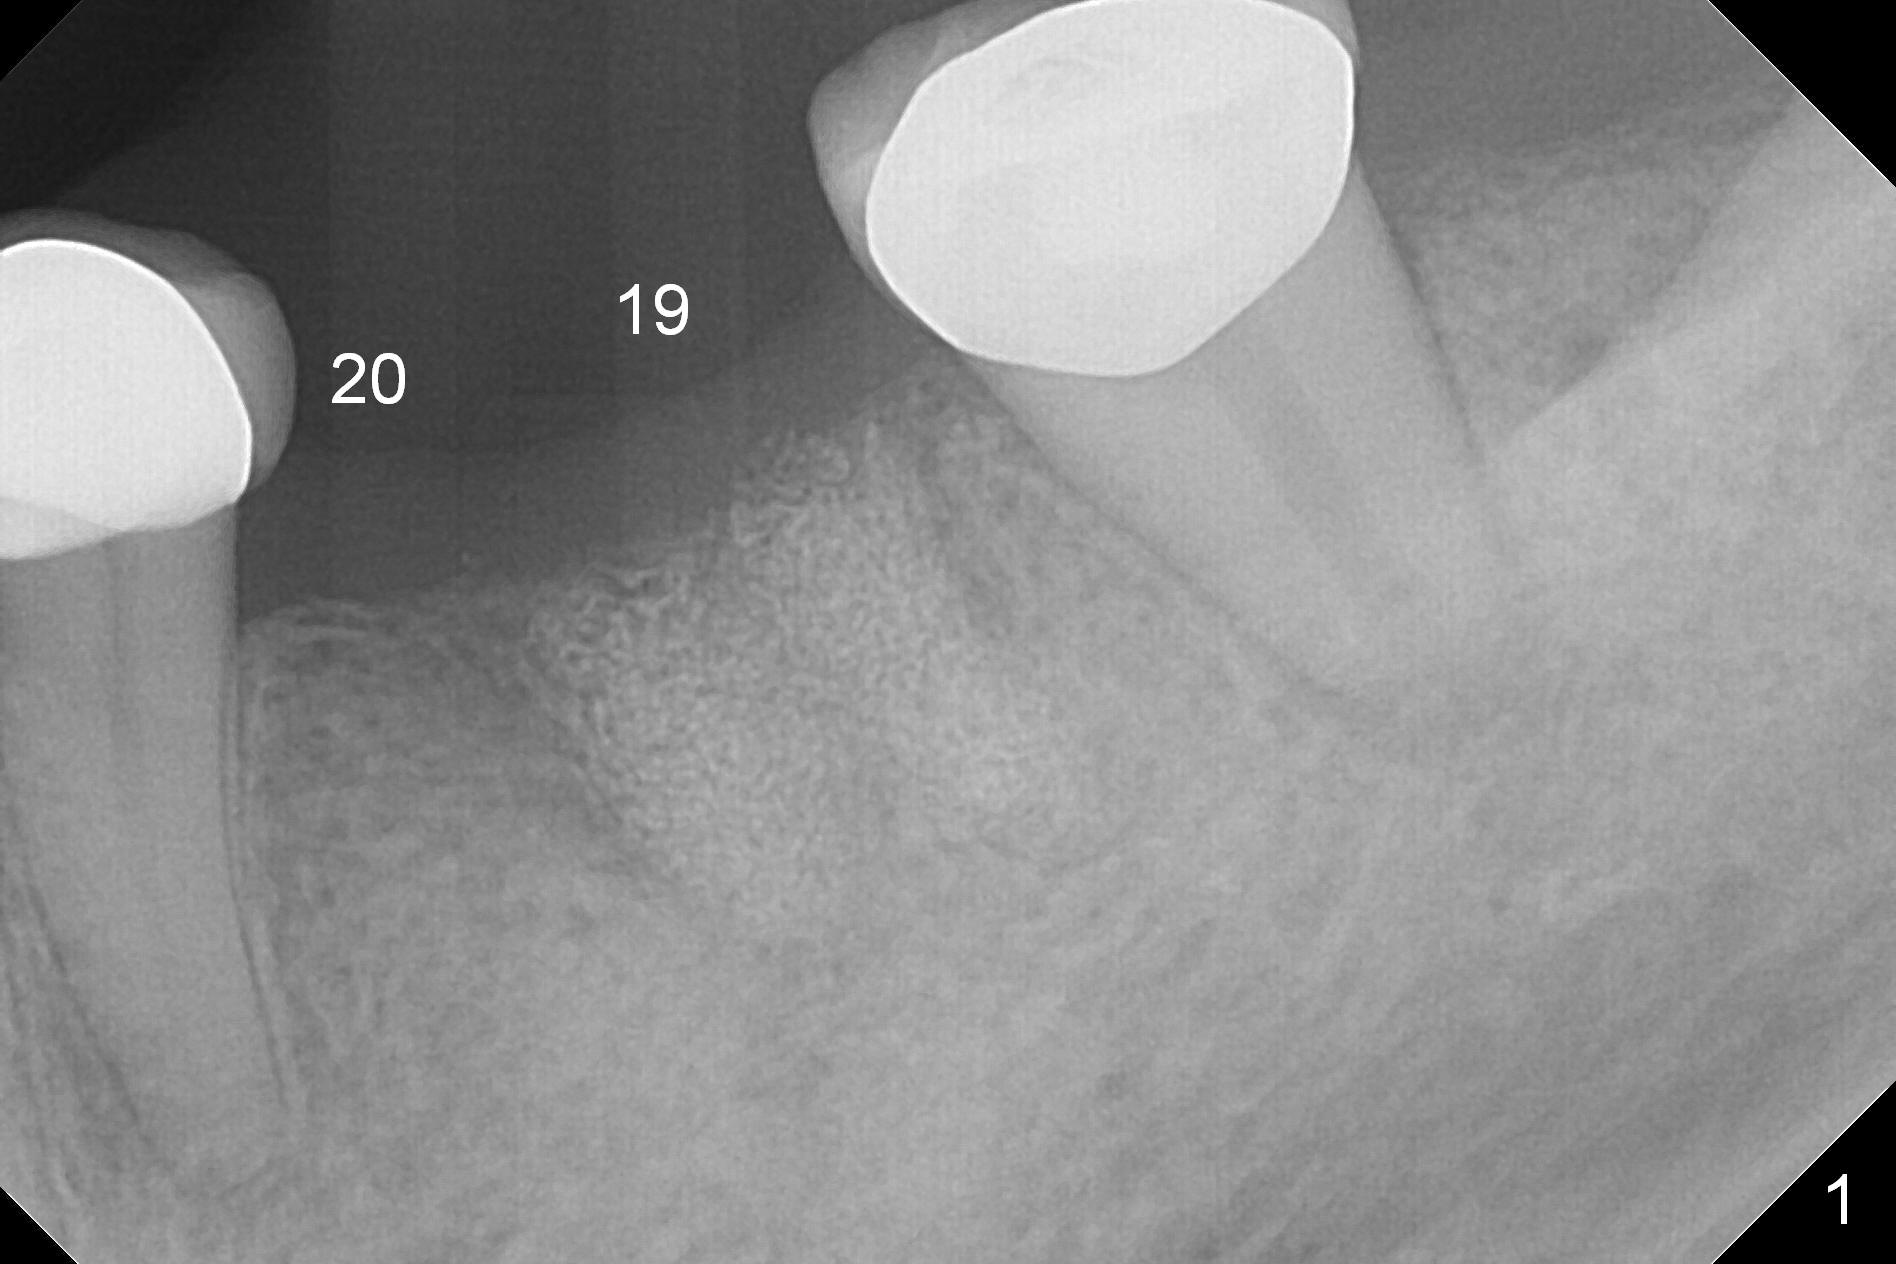

A 54-year-old woman requests implant placement at #19 six months post socket preservation with cow bone (Fig.1). The tooth #20 have been lost much longer. How many implants should be in the edentulous area?